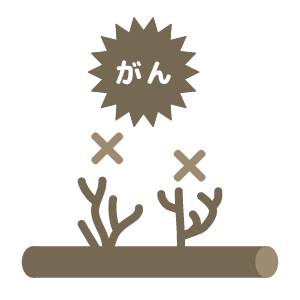

- がん細胞の生残りや変異があり、がん細胞をすべて死滅させることができない

- 免疫細胞ががん組織に到達できない場合も多い。

- がん組織が免疫不全状態になっていて、免疫細胞本来の力を発揮できない